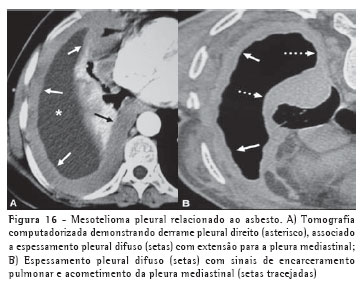

Mesotelioma

Apesar de haver descrições de mesotelioma em indivíduos com inflamação pleural crônica ou com história de exposição a carcinógenos químicos, a exposição ao asbesto está associada ao desenvolvimento do tumor em 50% a 80% dos casos. Dentre os achados radiológicos, o derrame pleural, geralmente unilateral, é o mais comum.

Podem também ser encontradas massas pleurais sólidas e espessamento pleural circunferencial com tendência a encarceramento pulmonar. A TC é o método de escolha na avaliação da presença e extensão do mesotelioma, apesar de os sinais não serem patognomônicos. Além destes achados descritos na radiografia, podemos encontrar espessamento irregular das fissuras, extensão para a pleura mediastinal, pericárdio e parede torácica e sinais de comprometimento à distância, como linfonodomegalias mediastinais, diafragmáticas e mamárias internas, e metástases linfáticas e hematogênicas (Figura 16).(21-22)